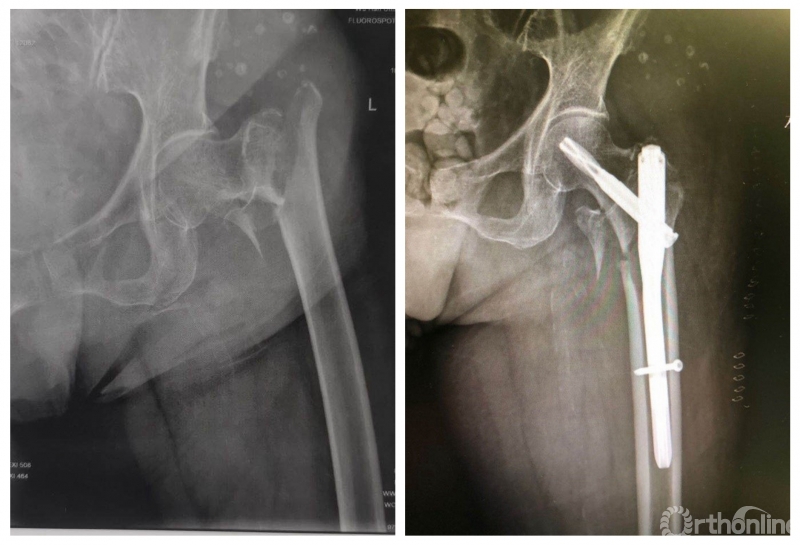

患者术前、术后影像对比

91岁高龄的姥姥入院后完善检查,无明显手术禁忌症,但如此高龄的患者给手术麻醉和病房护理也出了个大大的难题,刘国辉主任与麻醉科魏欣教授评估患者后,决定早期安排手术,避免长期卧床导致的褥疮、肺炎、下肢深静脉血栓等并发症。入院后第二日全麻下行PFNA微创手术,所幸手术及麻醉苏醒顺利,老人术后恢复良好,在病房的精心护理下术后开始早期下床功能锻炼。